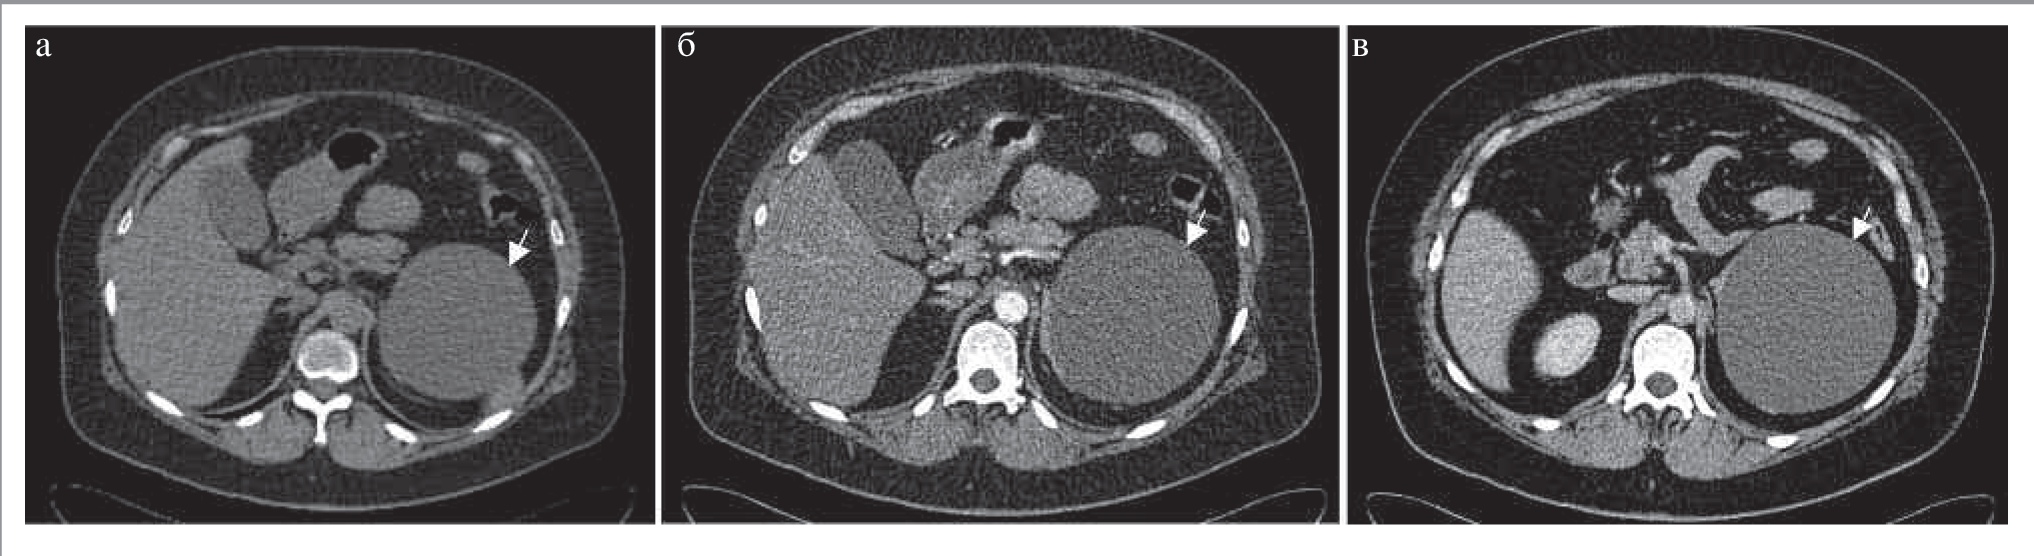

Эндотелиальные (простые) кисты представляют собой жидкостные тонкостенные образования, не накапливающие контрастный препарат, и составляют 45% случаев всех кист надпочечников (рис. 13) [33]. Среди простых кист выделяют лимфангиоматозные (42%) и ангиоматозные кисты (3%) [28, 33]. Чаще данные кисты диагностируются у женщин в среднем в возрасте 39,5 года. Средний размер кист – около 8,85 см. Данные образования являются гормонально неактивными, однако в литературе описаны единичные случаи гиперсекреции гормонов [35]. На КТ-изображениях киста представляет собой одно- (чаще ангиоматозные) или многокамерное (чаще лимфангиомы) образование с тонкими стенками, не накапливающее контрастный препарат (см. рис. 13). В стенках возможно наличие кальцинатов. Плотность содержимого лакун может быть повышенной ввиду наличия кровоизлияний или белкового компонента. Эхинококковая киста, феохромоцитома, нейробластома, шваннома, кистозные метастазы (например, рака молочной железы, яичников), первичная лимфома надпочечника – опухоли, которые могут иметь кистозный компонент, – должны быть включены в дифференциальный ряд.

Рис. 13. МСКТ, аксиальная проекция. Простая киста левого надпочечника (стрелка): а – НФ; б – АФ; в – ВФ.